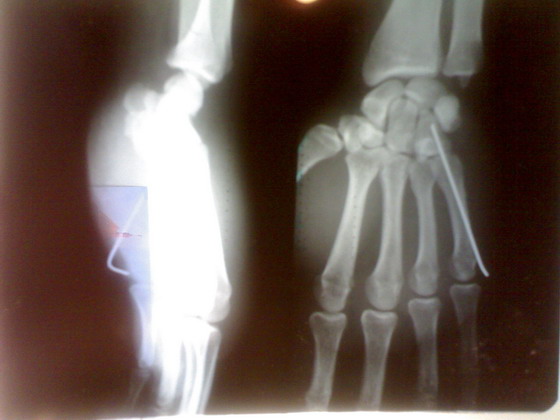

ДОБРОГО ДНЯ orthoforum,

предлагаю посмотреть интересный случай.

больной лечился в гипсовой лонгете 15

дней как ушыб.

правильный диагноз не был установлен.

я случайно взял эти снимки и посмотрел

поставил диагноз вывих 5 пясной кости.

некоторые колеги это сразу прямо перед

больным исключили даже

когда детально показал вывих своему

колеге.

после работы пациент меня нашел и

сказал что верит мне в

правильности диагноза.

больного я направил в область. его

прооперировали. вынесены

снимки.посмотрите.

после чего некоторые говорили что это

можно было б и неоперировать

а оставить так.

что скажут на этот случай уважаемые

колеги форума.